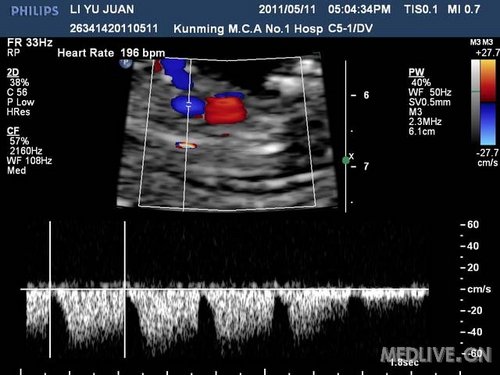

病史摘要:女,25岁,G1P0,从事化工工作,于11周+第一次产检,常规行NT检查时发现:胎儿面部扁平,脑中线显示不清,胎心快,根据FM提供软件计算13-三体风险值为39,建议孕妇绒毛活检,未同意,嘱两周后复查。

诊断为:全前脑,胎儿13-三体可能。建议绒毛活检,孕妇拒绝,要求引产,引产后大体标本与B超相符,取组织做染色体检查,证实胎儿为13-三体。